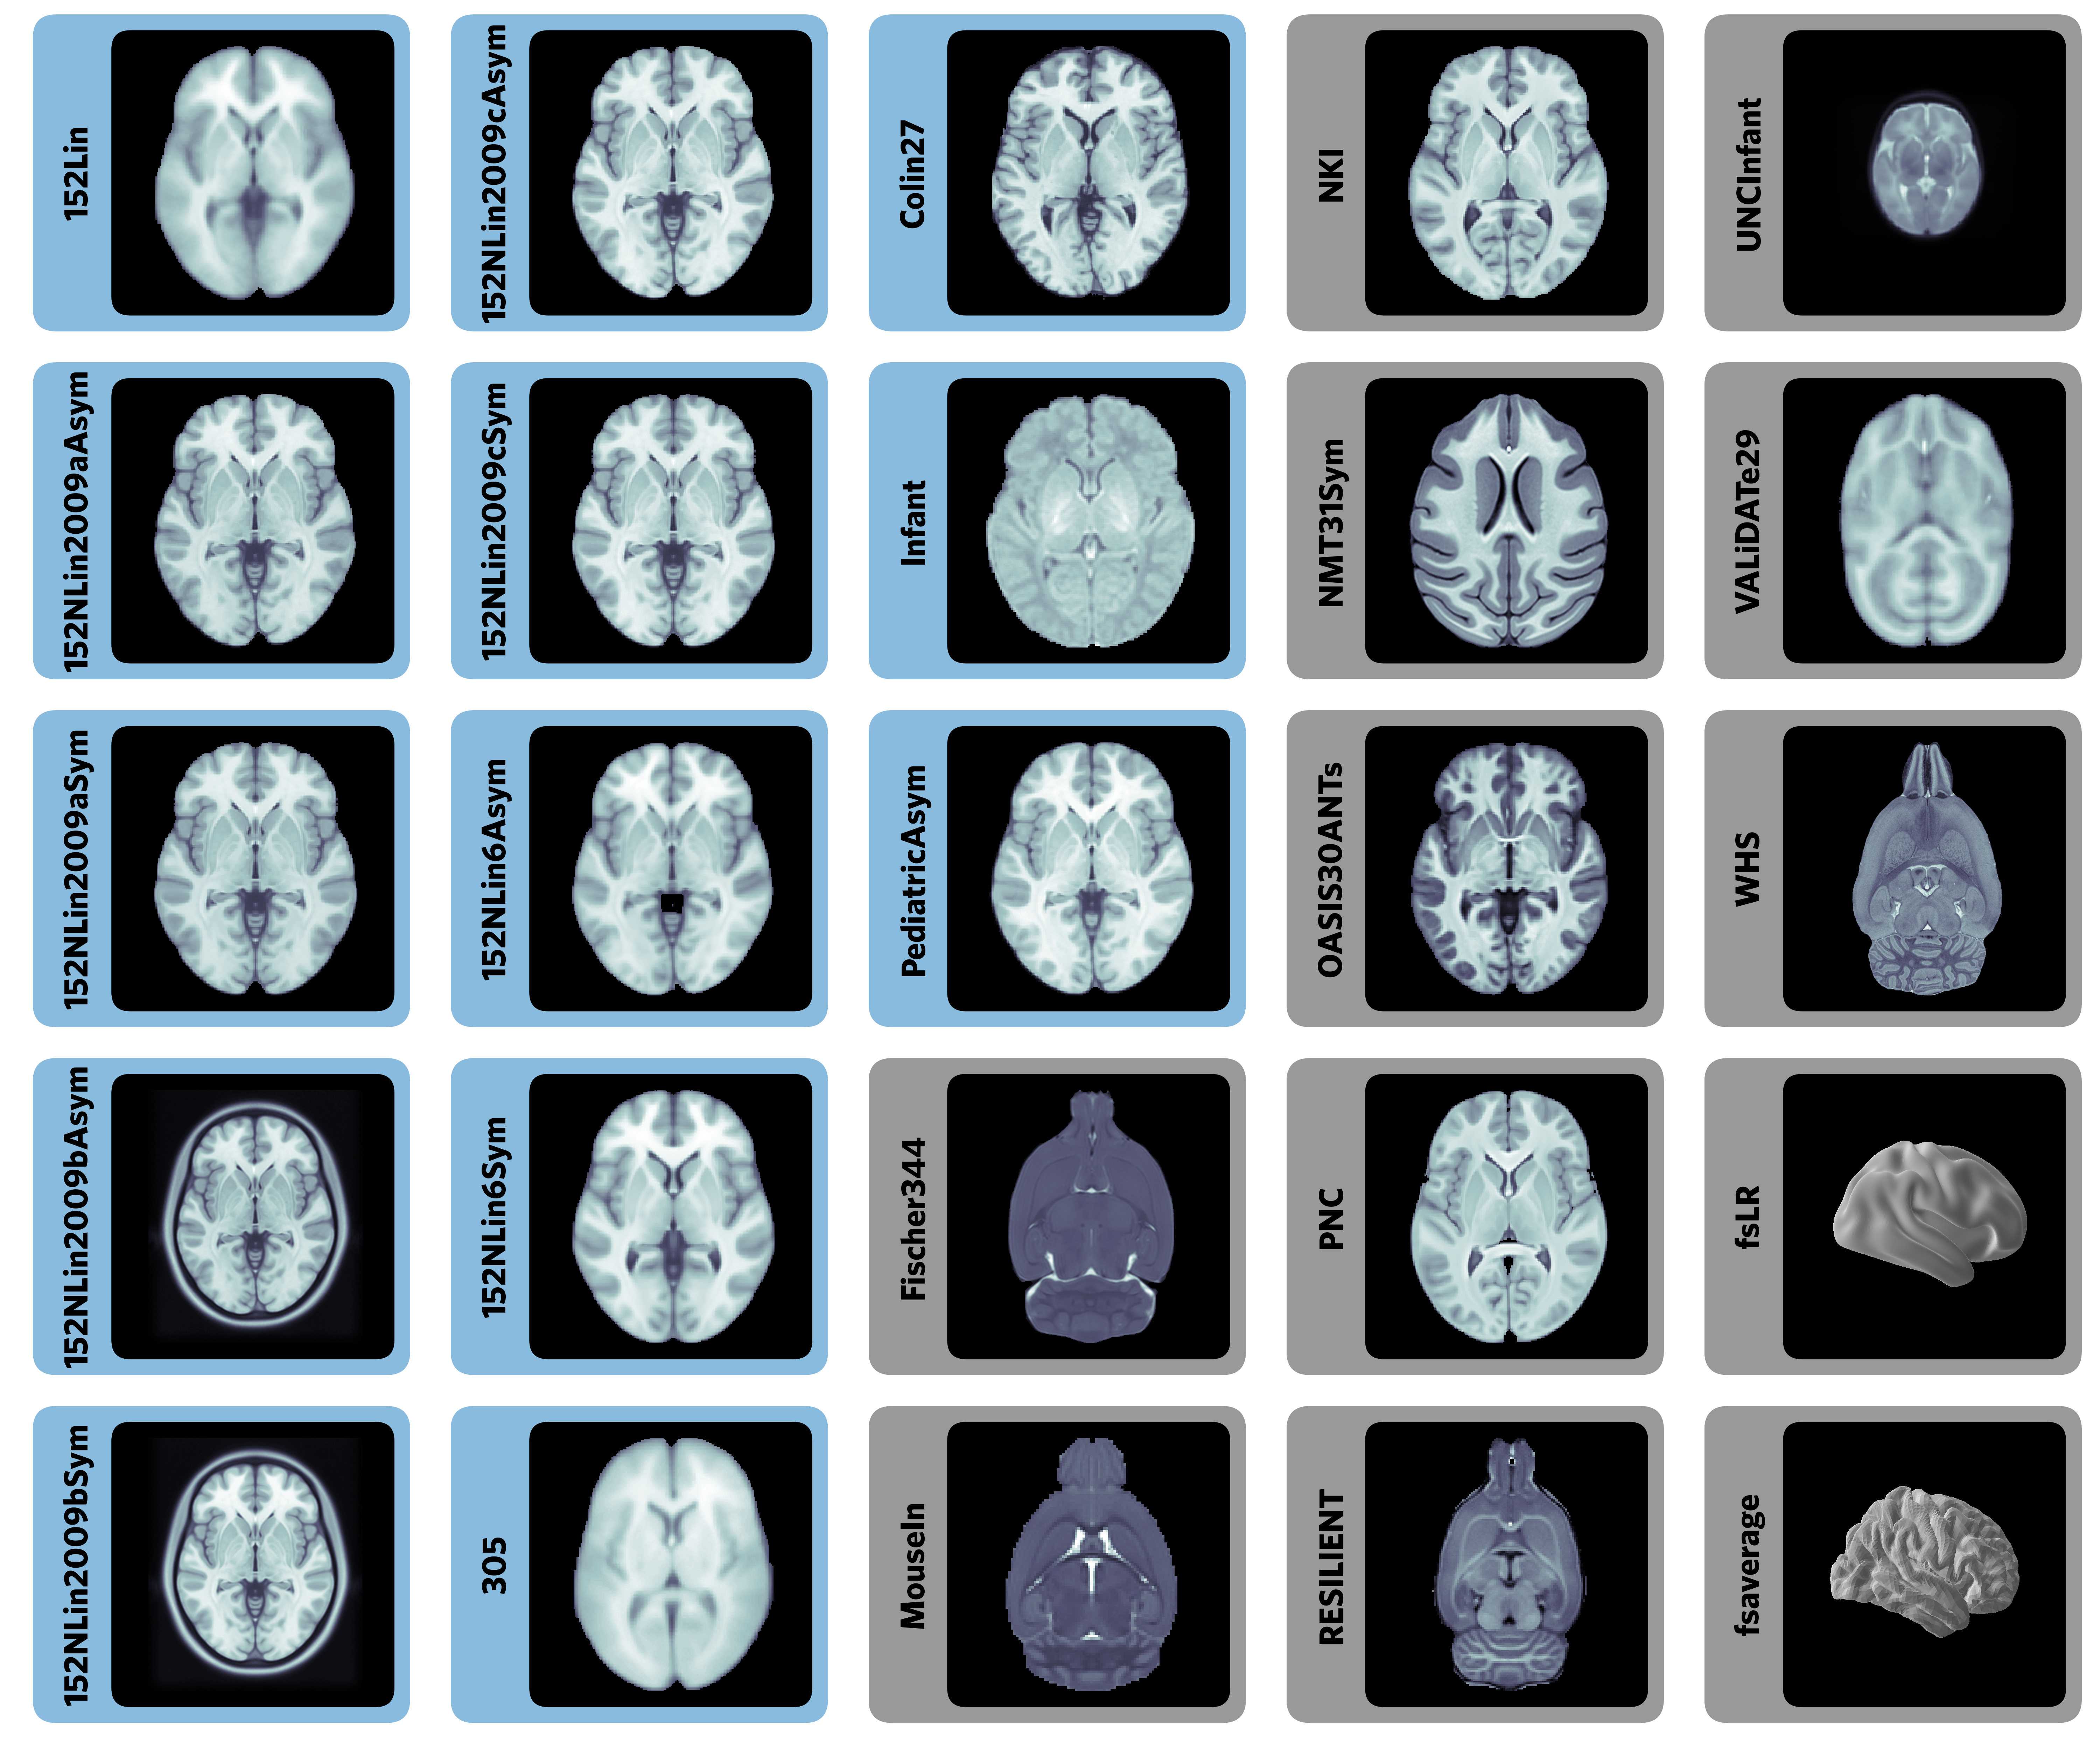

Templates and atlases are commonly used in neuroimaging research

There is significant lack of clarity in the use of these templates

Templateflow provides programmatic access to a database of templates and mappings between them